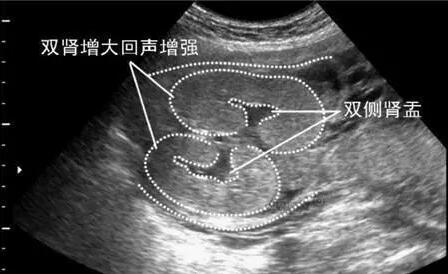

第三、如果四维彩超结果上有双侧肾盂未见明显分离,那么很高几率是女宝宝。如果是双侧肾盂见明显分离,那么很高几率是个男宝宝。这个是最容易判断生男生女的大排畸数据,准妈妈如果您做了大排畸可以仔细在B超单上找到这几个字“肾盂分离”或者是“肾盂无明显分离”。